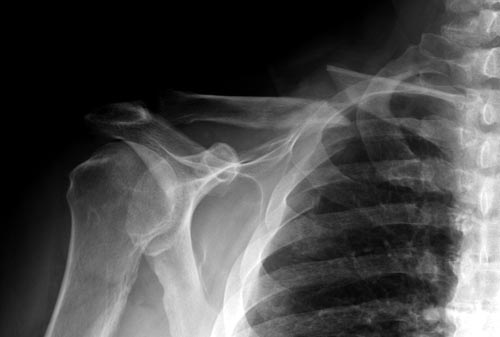

Уважаемые коллеги. Обратился пациент 29лет, оперирован в 2007 г. в Республиканском центре по поводу перелома ключицы и/м спицей, после несращения повторно оперирован в 2008 году, со слов больного освежение и повторно фиксация спицами, и обратился только через 6 лет, активные и пассивные движения в правом плечевом суставе в полном объеме, беспокоит только слабость при поднятии тяжести и подвижность в с/з ключицы. Р-снимок прилагается.Честно признаться, пока не знаю, что делать, имеются обычные пластины из ЦИТО, спицы, может, краевая резекция до появления «росы» дефект заполнить спонгиозной костью, фиксация и/м двумя спицами, загнуть оба конца спицы с компрессей, или пластина…или вообще не трогать. Прощу не критиковать, имеем то, что имеем, пациент в НИИТО не может ехать из-за финансов. С уважением Абдурашид.

Описанный Леонидом метод - выход из положения, но подойдет больше для лечения свежих переломов, чем для ложного сустава. Когда накостный остеосинтез был представлен только пластиной Лэна и доминировала идея “Decision Non Incision”, наружный фиксатор был универсальным фиксатором для всех видов переломов, включая открытые. Тактику считали правильной, и все публикации (диссертации) писали о преимуществе закрытого остеосинтеза. Но рекламируемое преимущество только до операции, потому что больше чем половину репозиций ключицы делают открытым методом. Отсутствует информация насчет осложнений и трудностей, например, установки спицы. Возможно, для Леонида или для врачей из Кургана это проблем не составляет, но для большинства не просто. Для сверления кости потребуется приподнять ключицу, и в результате разрываются мягкие ткани сзади. Это приводит к нарушению кровообращения сзади и поэтому такие операции часто осложняются дефектами кости!

Отсутствие фиксирующего материала усложняет дело, но в эру навигационной техники, роботов (DaVinci) и имея арсенал пластин, не стоит увлекаться не очень популярным методом! Пластины в сравнении со спицами лучше создают стабильность и межфрагментарную компрессию. Минимальное разрушение мягкотканого футляра происходит спереди, где пластина, что благоприятно влияет на сращение. А компрессия при фиксации спицей приведет к укорочению и дисбалансу мышечной системы. Пластина предупреждает укорочение и удерживает костный графт при необходимости.

В данном случае надо подождать, случай не ургентный! Тем более, у большинства со старым ложным суставом функцию конечности не теряется, и они бессимптомны. Боли бывают только в начальном периоде, затем интенсивность уменьшается, и к ним привыкают. К врачам они обращаются, когда имеется косметический дефект, или когда им напоминают о ложном суставе.

В заключение, только 25% изолированных переломов ключицы, леченных консервативным методом не срастаются, а из них 1/3 симптоматические. Болезненные ложные суставы надо оперировать, и здесь представлен случай свежего болезненного ложного сустава, оперированного через 4 месяца.

Освобожден средний фрагмент и боковая компрессия лагированием, фиксация пластиной..